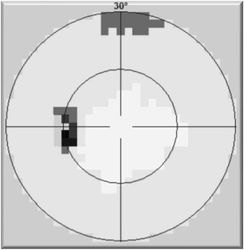

Vyšetření statickým počítačovým perimetrem - zorné pole před

Vyšetření statickým počítačovým perimetrem - zorné pole po